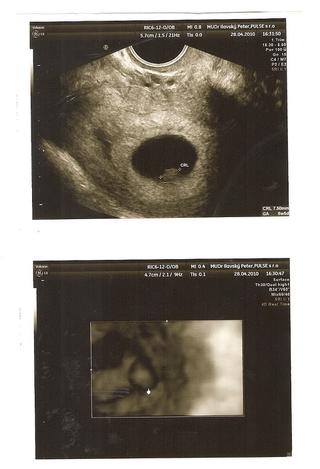

Ďakujeeeeeeem Vladka. Podľa PM som 7+2 a podľa sona 6+5

vladi prepac, pisala som to macke a viac som sa k pc nedostala...fakt enchapem, pri oliverovi mi takto stale zle nebolo...stale ma napina, jedine kde mi je dobre co sa cudujem je v aute ked soferkujem, ale velkym jamam sa musim vyhybat lebo je zlleee... 😀 no tak zatial mame 10mm teda mali sme, vyzera to ze zatoal vyzerame presne podla PM cize teraz 7+1...srdiecko nam bilo takze zatial ma moje nervy a stresy opustaju a mam aj obrazky len to musim cvaknut a stiahnut to sem, ale to asi az vecer stihnem, lebo idem este robit bublaninu, bo pride svokra a ja nemam ku kave nic doma..takl to bude take rychle..

Tehu bola som na pohotovosti, poobede som krvácala. No to jednanie o ničom, dokopy mi nikto nič nepovedal. No srdiečko bilo, som 7+3. Vraj mám nízko krčok maternice a na ňom léziu - nejaký nález ako pupák, alebo hánku čičo sama nechápem. No to som mala aj pri prvej tehotnosti. O týždeň mám ísť k svojmu, no pôjdem ráno. Vôbec mi nepovedal z čoho som zakrvácala. Teraz vraj budem krvácať z dôvodu vyšetrenia, tak hádam to nebude dlho.